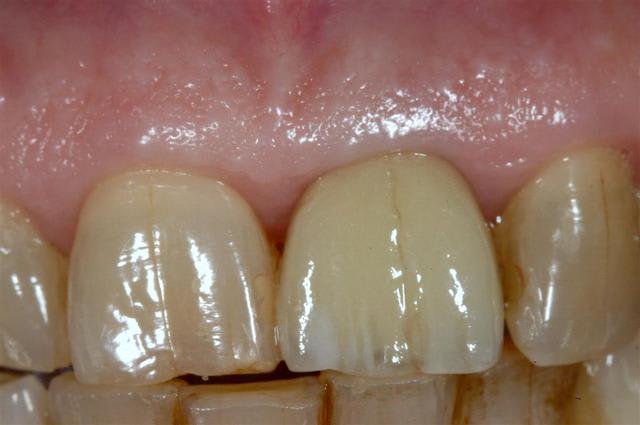

Cas simple, suite exo et greffe osseuse.

Bien vérifier axe avant de visser

La paroie buccale était absente lors de l'exo, kyste important, frature racines.

Allez, pour apporter mon caillou à la plage, un cas intéressant, d'implant en urgence.

consultation suite à une chute et fracture de 21 couronnée, un 29 Décembre, décision de poser l'implant le 31.12.

Extraction, mise en place d'un implant de 5*11.5 torque > 35N

Mise en place d'une dent provisoire transvisée.

Prothèse transvisée définitive à 3 mois.

Les 2 dernières photos à 1 an.

la photo ceram en place est à 6 mois. Noter l'amélioration des papilles entre 6 mois et 1 an...